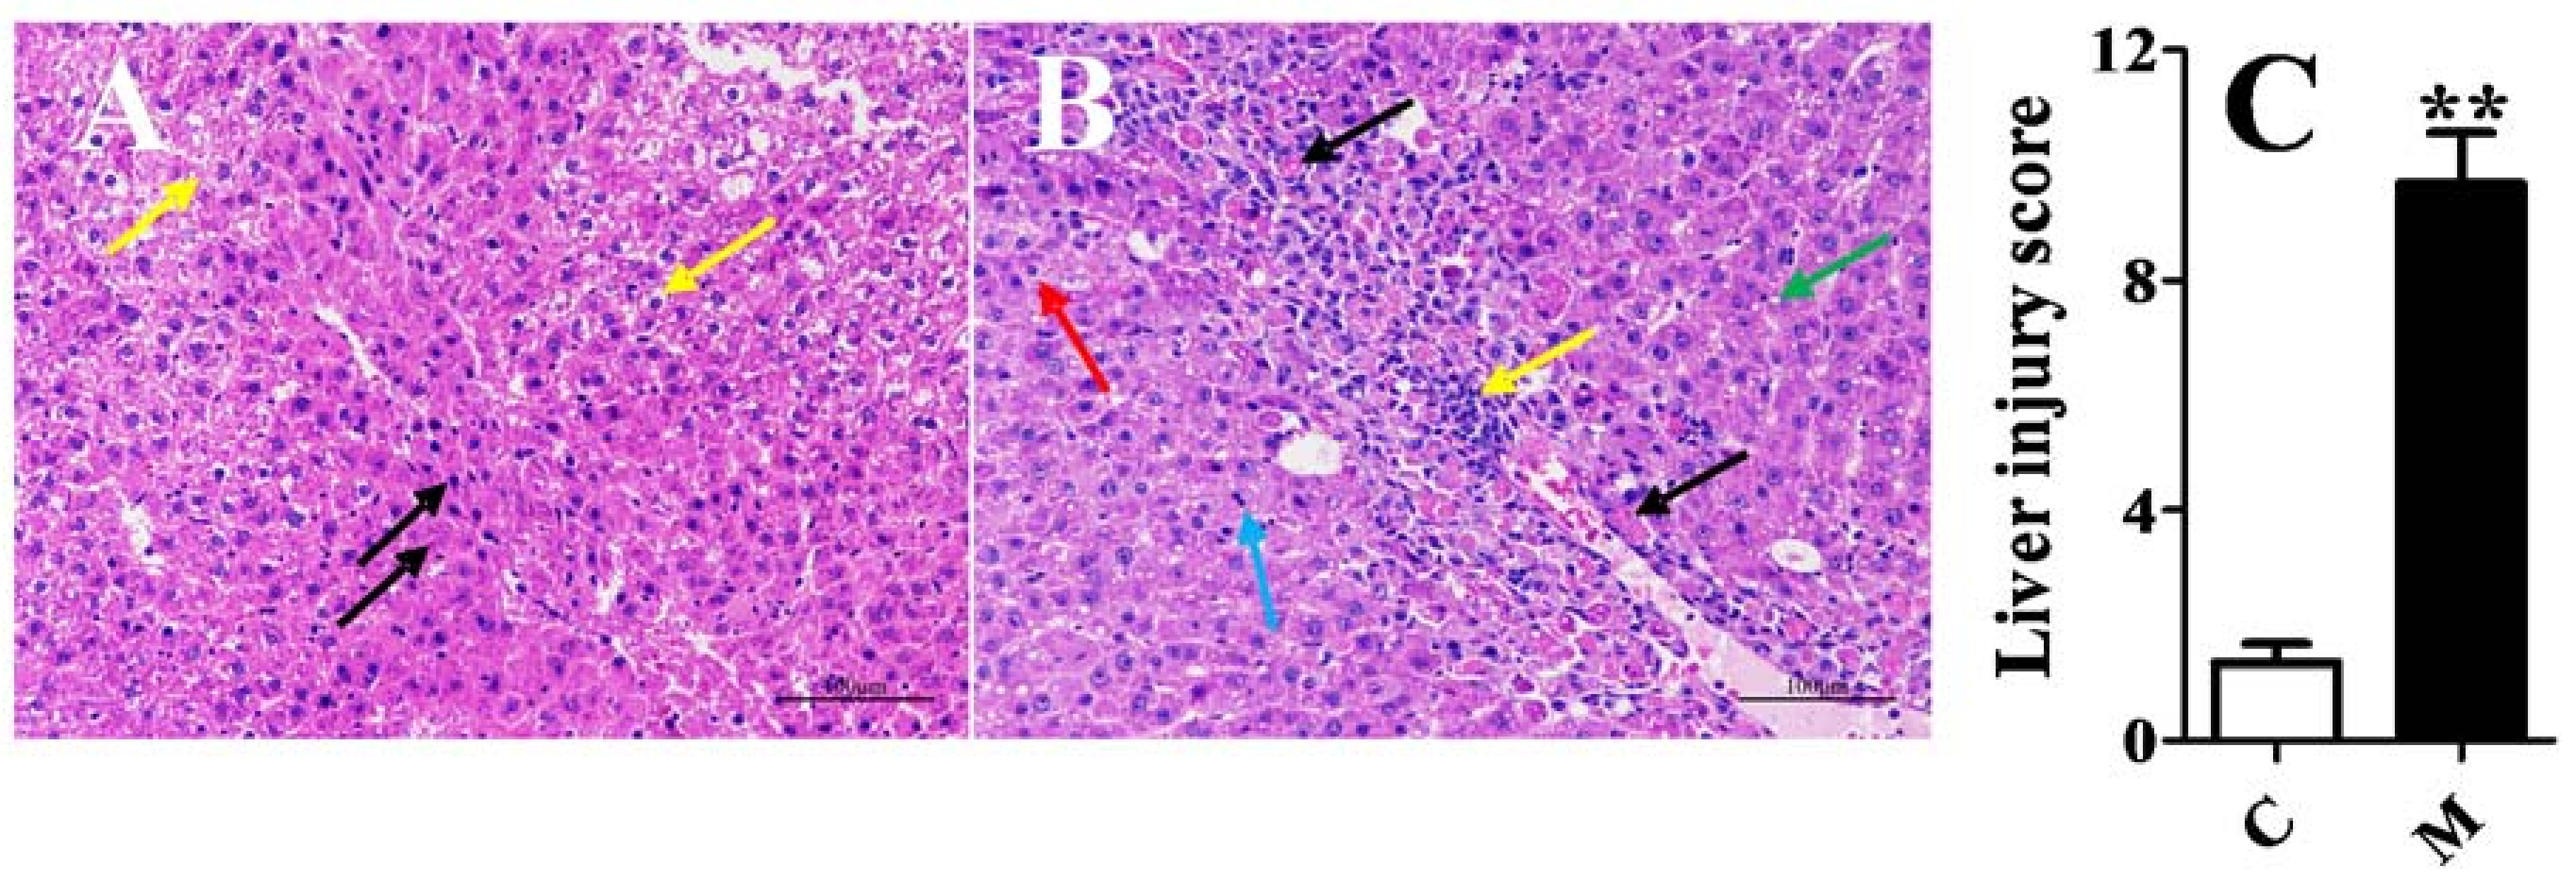

2.1. Validation of the Acute Liver Injury Rats Model

3.3. Animals and Induction of Acute Liver Injury